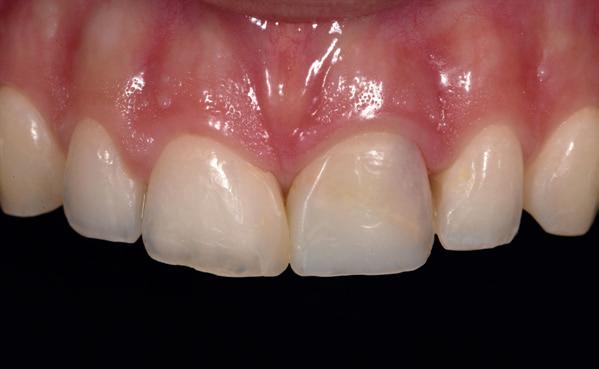

Voor een vaste brug is het belangrijk dat er zo spoedig mogelijk na de (totaal)extracties wordt gestart met het implanteren en de kaakverbredingen, het liefst immediaat. Hoe verder de resorptie gaat, des te meer roze porselein gebruik nodig is. Tegenwoordig wordt er geen porselein meer gebruikt, maar wordt het zirkoonoxide roze ingekleurd. Alleen bij immediaat geplaatste implantaten en direct een tijdelijke brug om de weefsels te ondersteunen, kunnen de witte elementen en de roze mucosa in harmonie zijn zoals in de natuurlijke situatie. Carl Misch (1993) heeft dit in zijn boek beschreven als Fixed Prosthodontics 1 (FP1). Is er verticale resorptie van weefsels, dan moet een compromis worden gekozen tussen onnatuurlijke lange elementen (FP2) of een combinatie van elementen met roze inkleuring van de mucosa (FP3).

Gezien er in deze casus eerst gekozen moest worden

voor een noodprothese, omdat er spoed was en de parodontale ontstekingen in de onderkaak tegelijk behandeld moest worden, werd hier gekozen voor een compromis met FP3 als vaste brug.